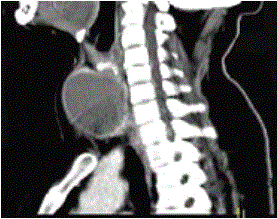

问题 女,56岁,发现颈部肿块30天,颈部肿大,无红肿热痛,无呼吸困难,无吞咽困难,无心悸胸闷烦躁史。近1个月来因肿大不适而来就诊。发病来饮食睡眠正常,体重无下降。如图所示该患者最可能诊断为()

选项 A.甲状舌管囊肿 B.甲状腺乳头状癌 C.甲状腺原发淋巴瘤 D.甲状腺腺瘤 E.甲状腺脓肿

答案 D